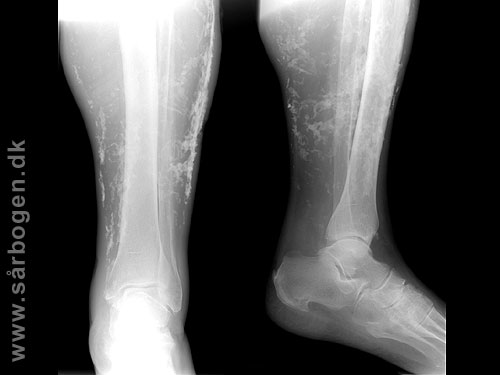

Subcutane Kalcifikat...

Zoom